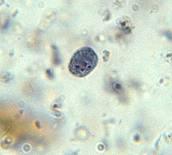

微小內蜓阿米巴

Endolimax nana

有滋養體和包囊期,外形大小很象哈門氏內阿米巴。滋養體直徑6~12µm ,核有一粗大明顯核仁而無核周染色質粒。胞質量少,顆粒狀並含空泡,核膜與核仁之間有清晰的空間和相連的核絲。包囊小,卵圓形,無擬染色體,偶見形狀不一的糖原泡,成熟包囊含四核,直徑為5~10µm ,一般認為無致病性。該蟲體積比哈門氏內阿米巴小,且有粗大核仁。胞核與布氏嗜碘阿米巴相似,但包囊較小,微小內蜓阿米巴寄生在人、猿、猴和豬等的結腸內,滋生繁殖,它們的生活史與溶組織內阿米巴相同,人通過污染的水和食物而